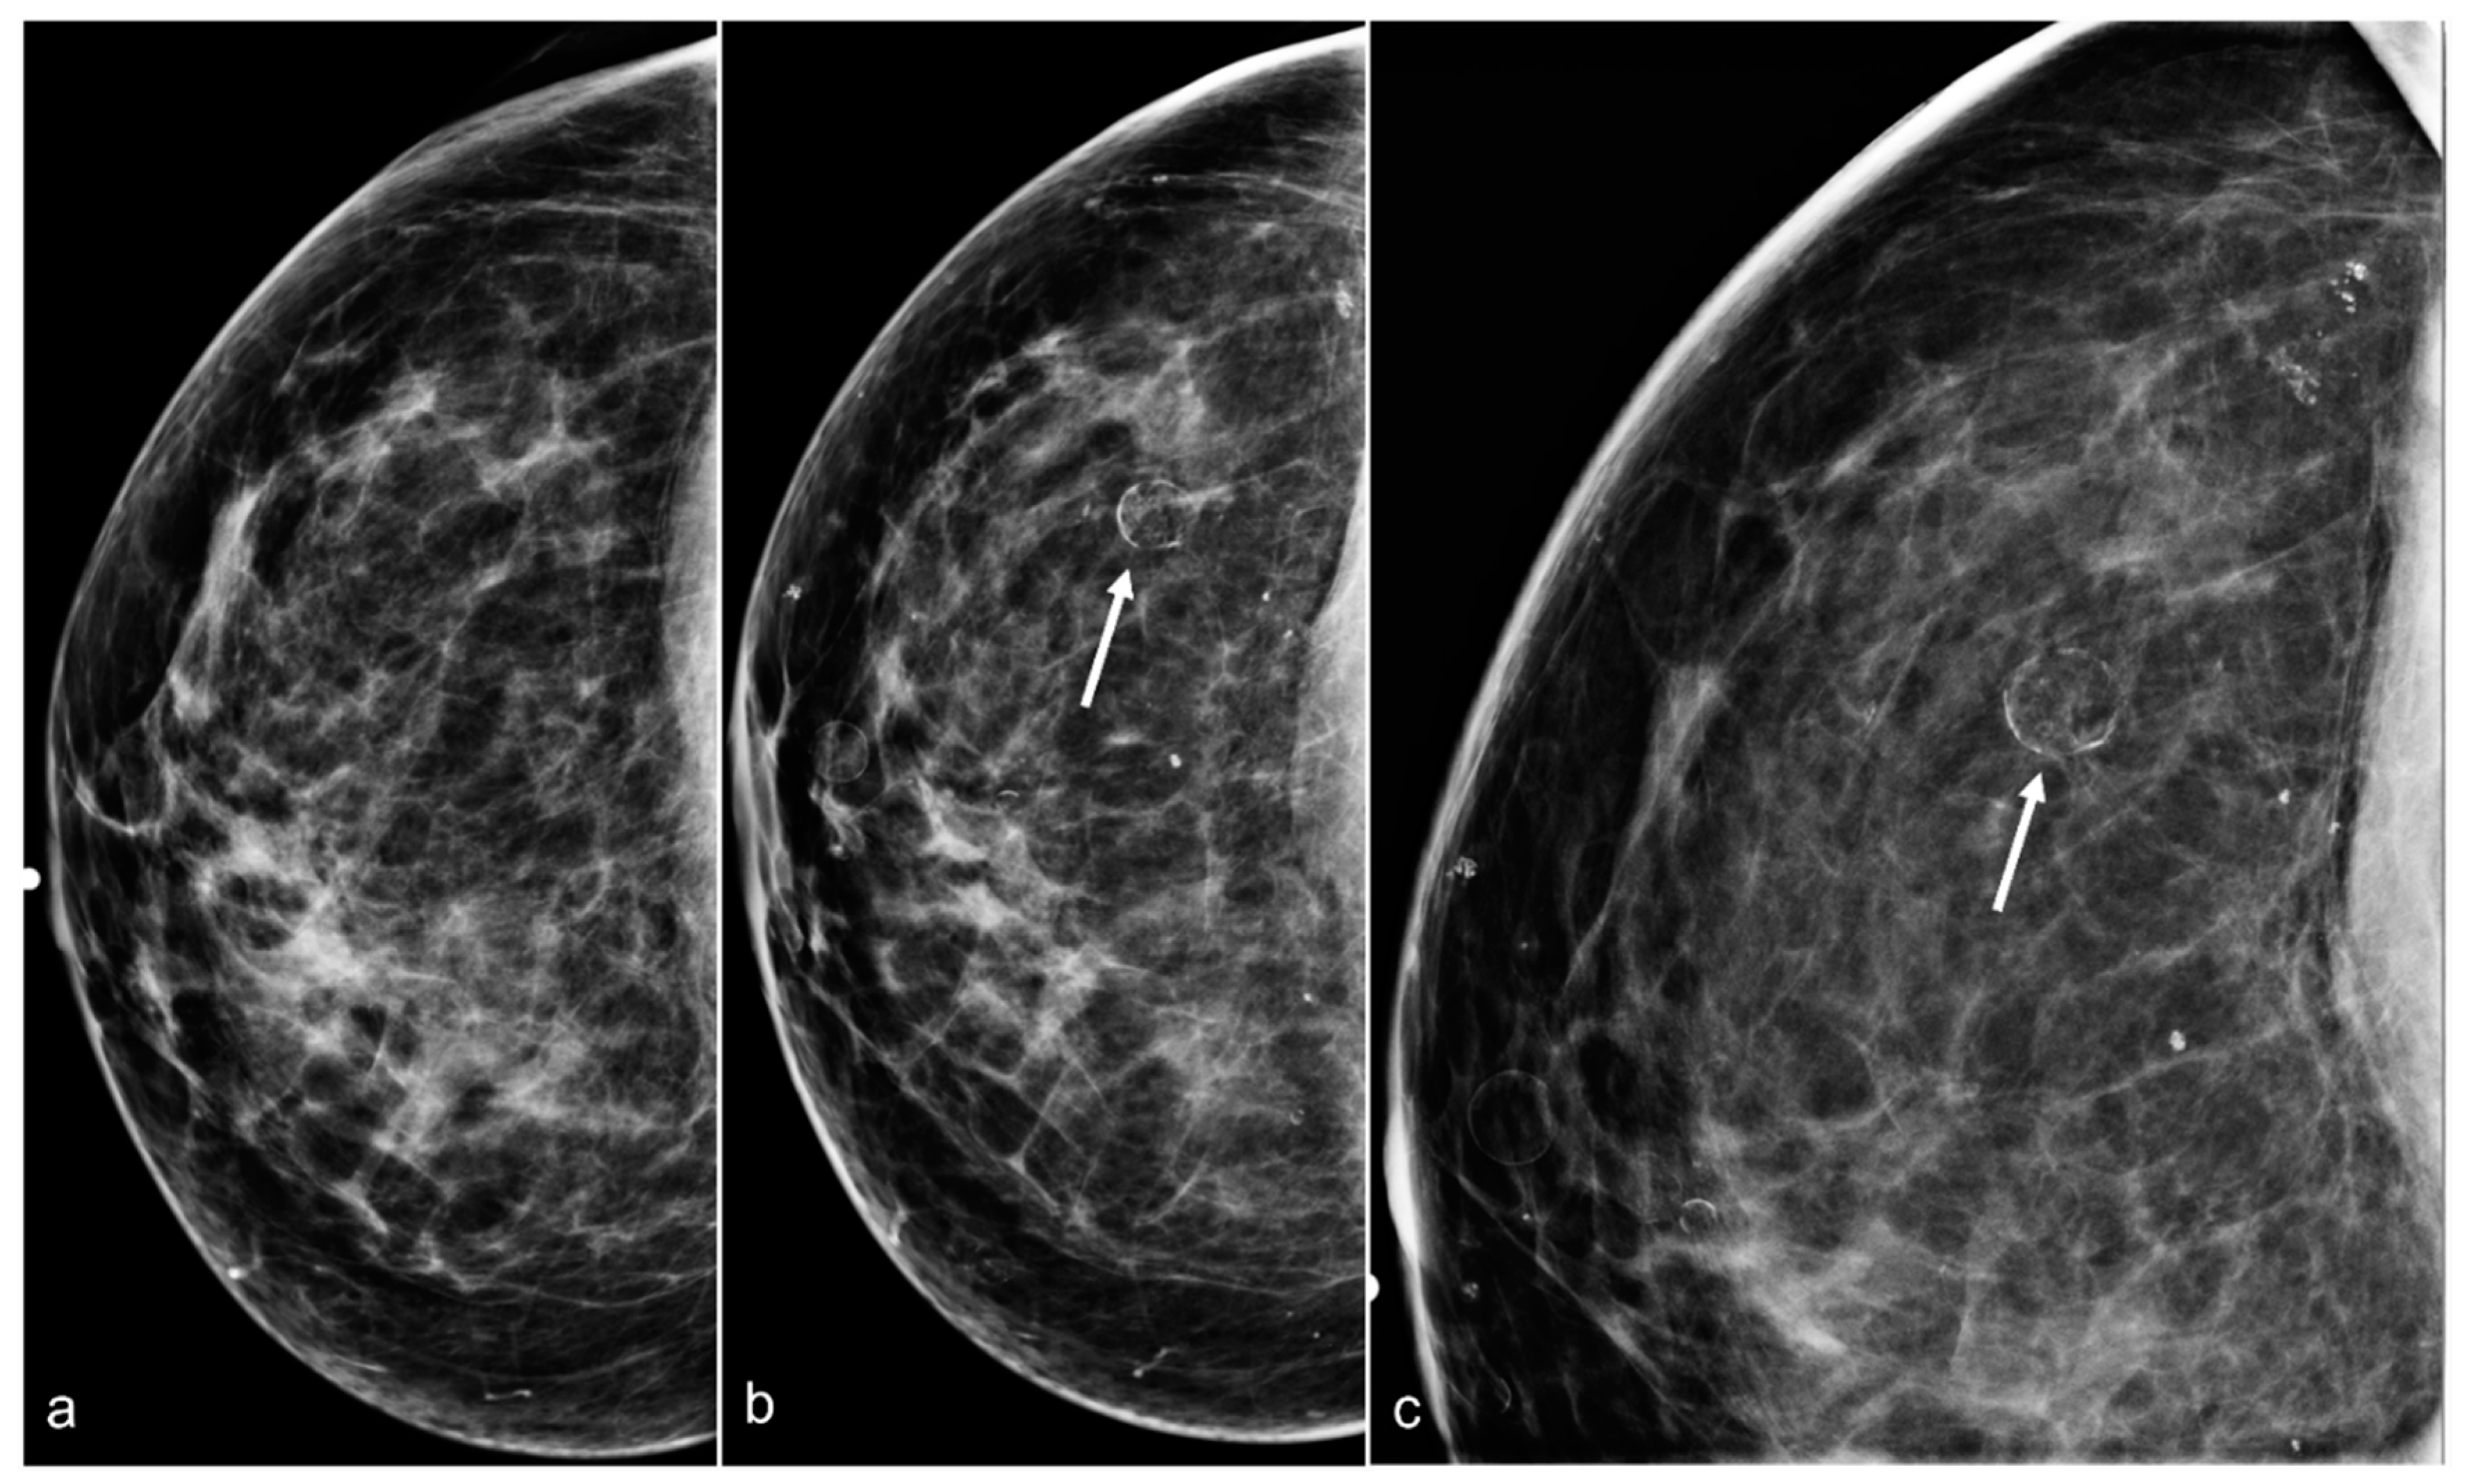

Figure 5. A 54-year-old woman with a history of subglandular silicone implants. Right breast CC view (a) performed 2 years after BES and mammogram performed 3 years after BES CC (b) and magnified CC (c) views demonstrate developing oil cysts (arrows) in the right breast.